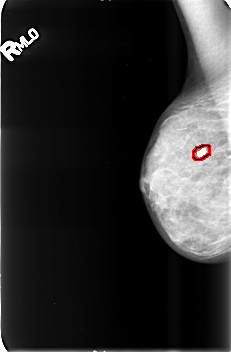

B_3428_1.RIGHT_MLO

FILE: B_3428_1.RIGHT_MLO.OVERLAY

TOTAL_ABNORMALITIES 1

ABNORMALITY 1

LESION_TYPE CALCIFICATION TYPE COARSE DISTRIBUTION N/A

ASSESSMENT 2

SUBTLETY 5

PATHOLOGY BENIGN_WITHOUT_CALLBACK

TOTAL_OUTLINES 1